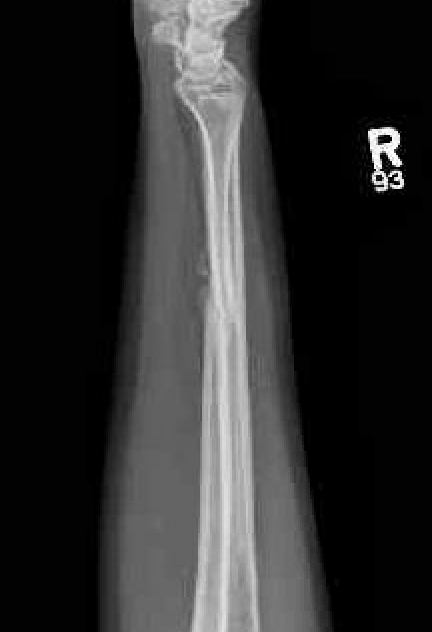

Complications

nonunionnonunion

Ulna nonunion after plating